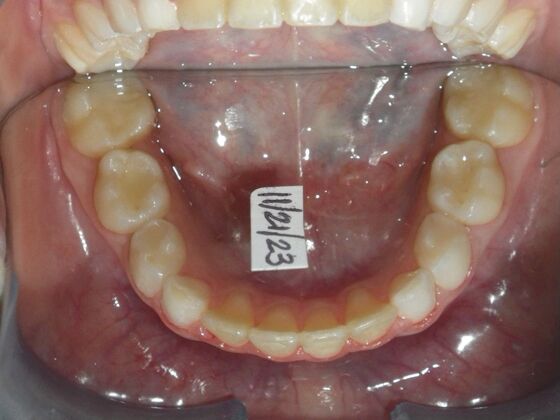

This sweet patient presented with constricted upper and lower arches and blocked out, rotated upper and lower anterior teeth. The upper centrals were leaning backward and had the lower arch captured preventing anterior advancement. Treatment was begun on the upper arch first, followed with placement of lower lip bumper to allow for lateral and anterior development of lower arch. Eventually placed lower brackets with strategic slenderizing of primary teeth to allow permanent incisor to assume their proper placement. All accomplished within 12 months and straight-wire appliances.